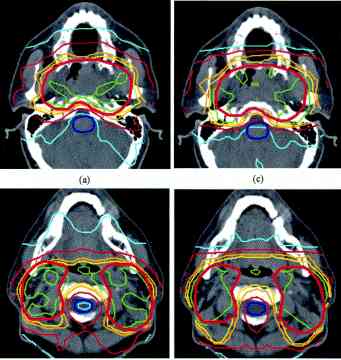

radiation isodose #1 , #2, #3, #4, #5 |